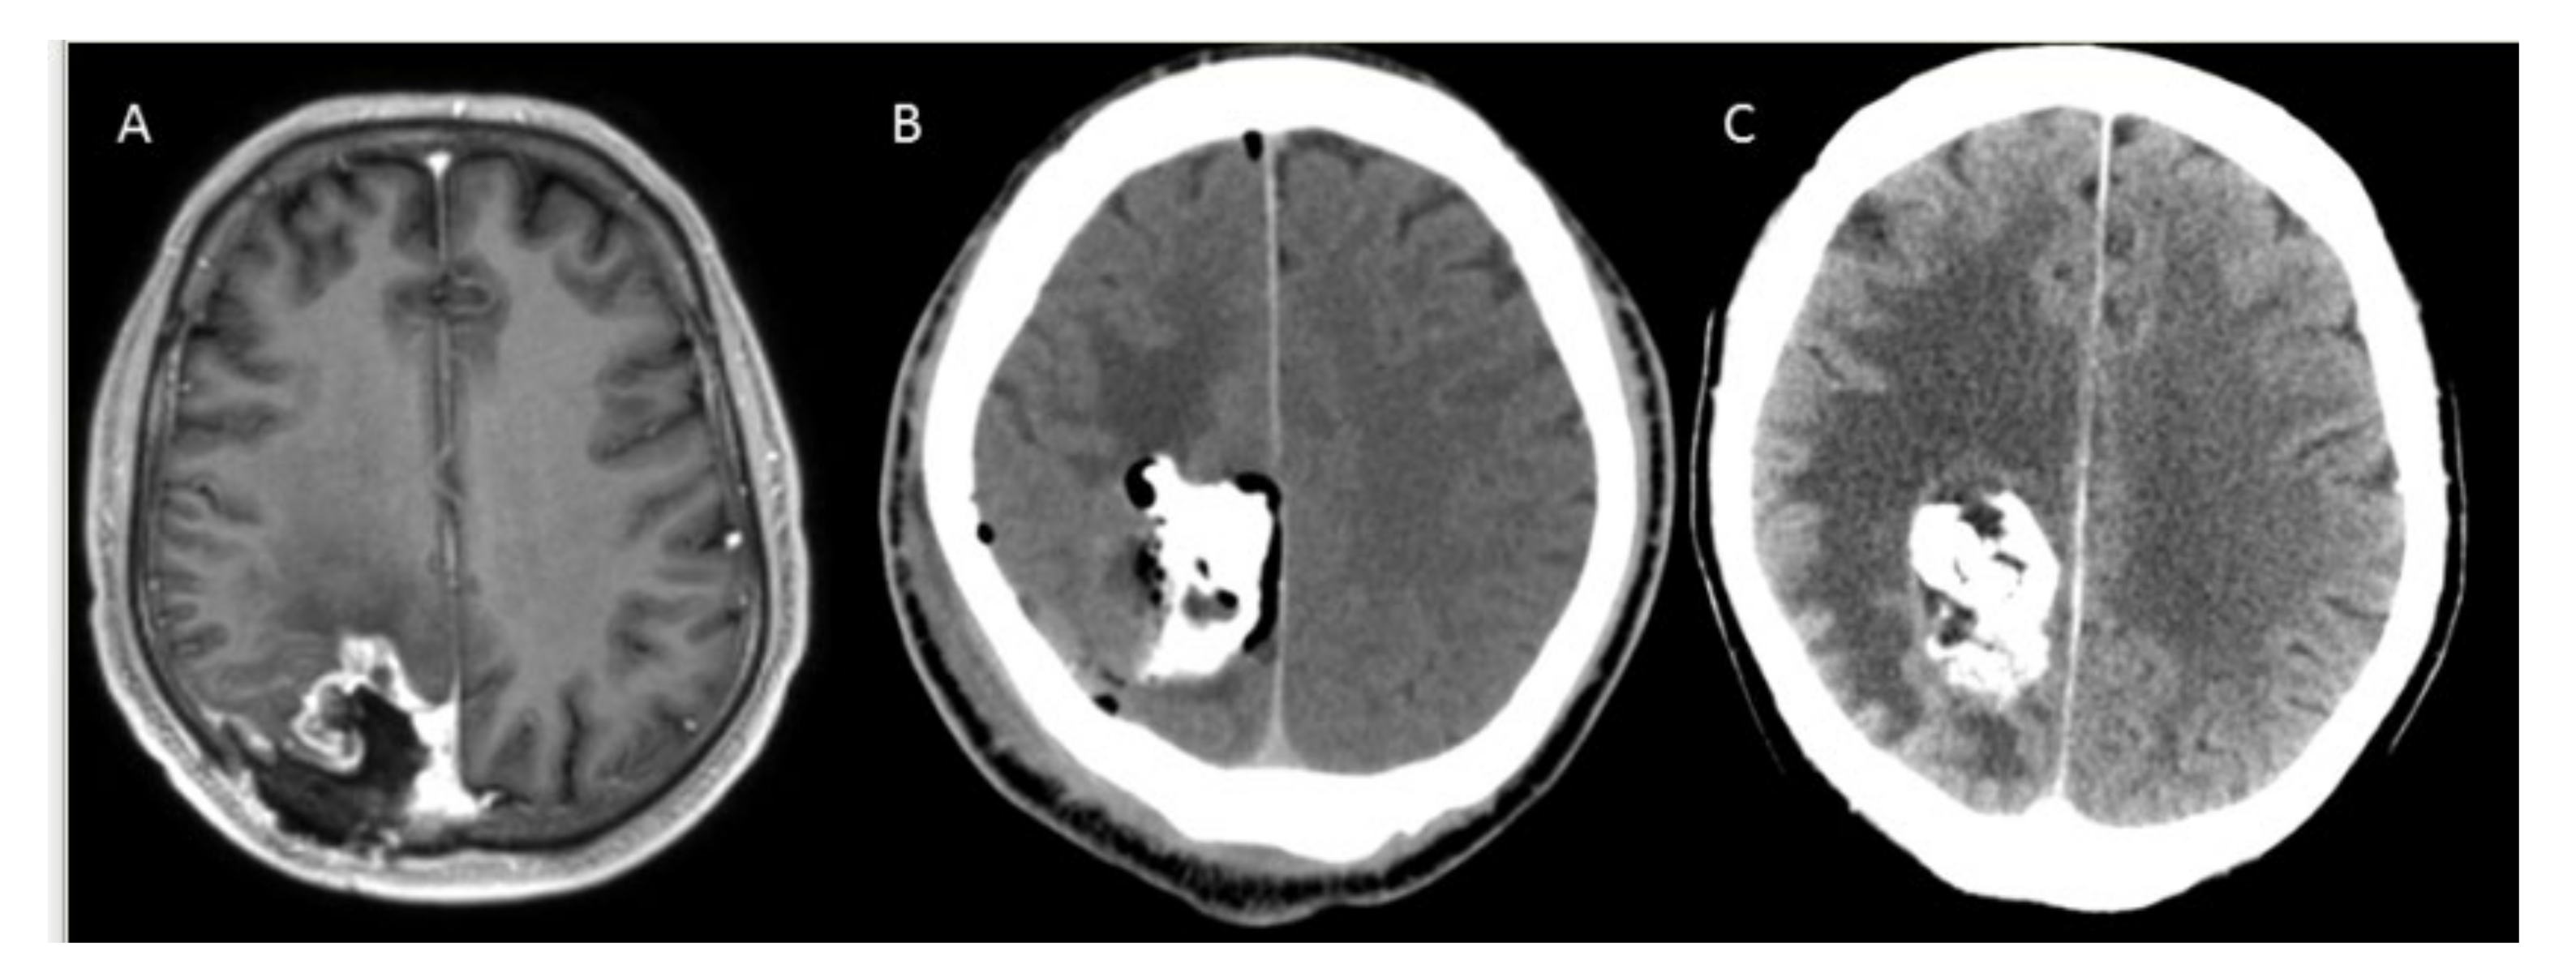

- Grauer, O.; Jaber, M.; Hess, K.; Weckesser, M.; Schwindt, W.; Maring, S.; Wölfer, J.; Stummer, W. Combined intracavitary thermotherapy with iron oxide nanoparticles and radiotherapy as local treatment modality in recurrent glioblastoma patients. J. Neurooncol. 2019, 141, 83–94. [Google Scholar] [CrossRef] [Green Version]